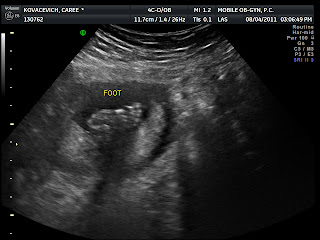

it's a B.O.Y!!

No more sea monkey!! Hello human baby!!!!